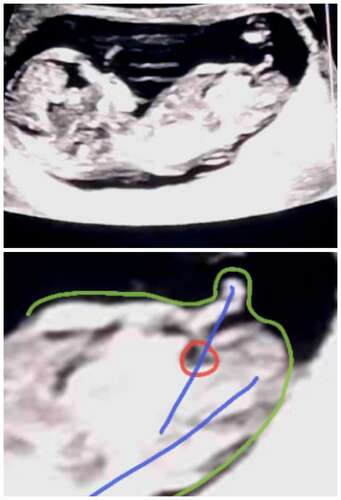

Onderste foto is de nub van dichtbij.

Groen: de omranding van de kleine

Rood: de blaas

Blauw: de stand van nub en blaas in vergelijking met de ruggengraad

(📐) staat het in een hoek van de ruggengraad wijst het op een jongen.

(=) staat het gelijk of bijna gelijk aan de ruggengraad wijst het op een meisje.

Daarnaast is een bolletje boven de nub wat je bij jouwn echo hebt het deel wat langzaam de pipi word terwijl de lijn eronder langzaam veranderd in de balletjes. Bij meisjes zie je geen bolletje erboven daar is de nub een lijn. De blaas zal als het goed is nog iets verder zakken. Maar dat komt door het termijn waarin je zit dat het nog niet allemaal op de plek zit.